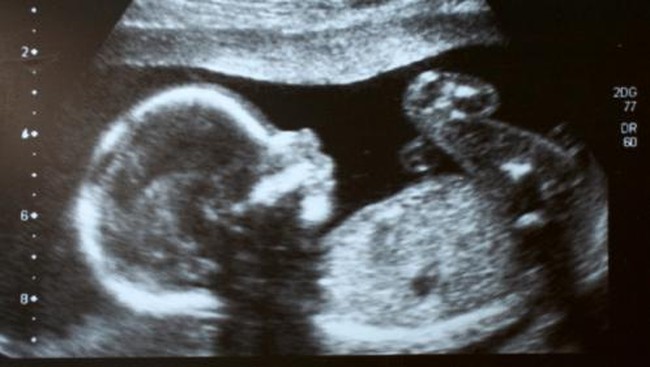

Faktor-faktor yang Pengaruhi Aktif atau Pasifnya Gerakan Janin

Jakarta - Dapat merasakan gerakan bayi ketika dalam kandungan merupakan hal yang luar biasa bagi ibu. Meskipun, gerakan si kecil di dalam kandungan pun bermacam-macam.

Ada bayi yang aktif bergerak, tapi ada pula yang pasif. Ketika bayi yang pasif bergerak, situasi ini kadang menimbulkan kekhawatiran pada ibu terkait kondisi sang bayi.

Sebenarnya, ada bayi yang aktif dan pasif bergerak dipengaruhi pula oleh berbagai faktor. Apa saja? Simak pemaparannya seperti dirangkung detikHealth dari berbagai sumber berikut ini.